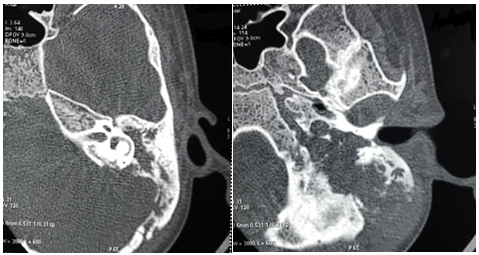

Patient was admitted and started on empirical intravenous antibiotics. Mantoux test was negative. An attempt of lumbar puncture was unsuccessful. High Resolution Computed Tomography of temporal bone was suggestive of an ill defines iso-dense heterogeneously enhancing lytic expansile lesion involving left jugular bulb causing erosion of squamous part of temporal bone, clivus, mastoid part of temporal bone with thrombosis of left sigmoid sinus and internal jugular vein (Figure 1). Post contrast Magnetic Resonance Imaging of brain revealed an ill-defined moderately heterogeneous enhancing lesion of left jugular bulb causing erosion of squamous part of occipital bone and extending into pre and para vertebral space up to level of C1 vertebra and causing destruction of mastoid part of temporal bone with thrombosis of left sigmoid sinus and internal jugular vein (Figure 2). Cranial Magnetic Resonance Imaging venography showed thrombosis in left sigmoid sinus and internal jugular vein (Figure 3). Blood investigations ruled out the presence of hypercoagulable state in our patient.

Figure 2 Post contrast Magnetic Resonance Imaging of brain: Destruction of mastoid part of temporal bone with erosion of squamous part of temporal bone and thrombosis of left sigmoid sinus and left internal jugular vein.